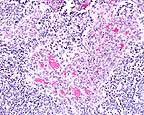

Characteristic "glomeruloid" vascular proliferation seen in high-grade astrocytomas, due to the effect of vascular endothelial growth factor by neoplastic cells.(HE, 200X, 85K)

Higher magnification of vascular proliferation in a highly cellular area of the neoplasm. (HE, 200X, 123K)

Astrocytomas generally occur as soft tissue masses in the substance of the cerebral hemispheres, and produce a spectrum of clinical signs based on their exact location. The majority of astrocytomas are well-differentiated with a relatively uniform population of transformed astrocytes having oval nuclei, little heterochromatin and poorly defined cell borders. The tumors can be graded, but regardless of grade there is a background of astrocytic processes between neoplastic nuclei. Higher grade astrocytomas are characterized by increasing nuclear anaplasia, mitotic activity and vascular proliferation. In the adjacent parenchyma, endothelial cells may form glomeruloid proliferations within vascular lumina. These are prominent in high grade astrocytomas, and were present in this case. The highest grade astrocytomas are usually very cellular, and have a mixture of firm white areas, and softer yellow foci of necrosis. These latter features, especially the presence of necrosis, have given rise to the term glioblastoma multiforme. Immunohistochemistry performed by AFIP was positive for glial fibrillary acidic protein (GFAP) and negative for S100, synaptophysin, cytokeratin, and vimentin.

Conference Note: This case has classic features of glioblastoma multiforme, which is often simply called high grade astrocytoma. These features include high cellularity, pleomorphism, necrosis, subpial spread, cortical infiltration, necrosis surrounded by "pseudopalisades" and areas of glomerulus-like endothelial proliferation. Recent evidence suggests that vascular endothelial cell growth factor (VEGF) is secreted by malignant astrocytes perhaps in response to hypoxia.